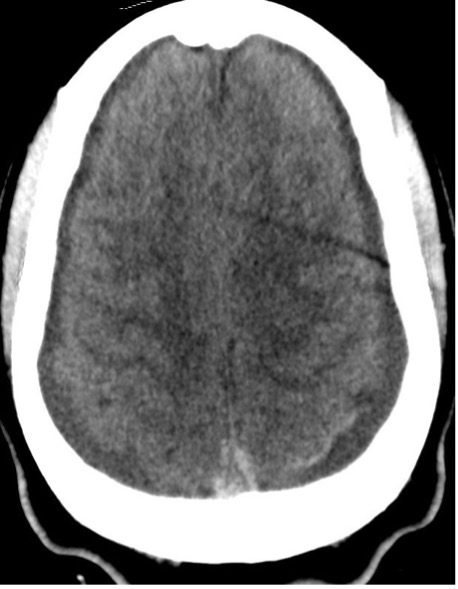

Diagnostic Testing. The patient’s CT brain imaging revealed a small amount of air in both frontal horns of the lateral ventricles (Figure 1). Her brain CTA revealed distension of the superior sagittal sinus (SSS), inferior sagittal sinus, transverse sinus, and vein of Galen and an extra-axial SSS defect (Figures 2-4). The initial report of the MRI brain with and without contrast redemonstrated trace pneumocephalus but was otherwise unremarkable. Later review after 10 days, revealed pachymeningeal enhancement, venous sinus distension, and a filling defect in the SSS suggestive of venous sinus thrombosis (Figures 5, 6). Her MRI of the cervical spine did not reveal another cause of neck pain, and her urine protein was negative.

Fig. 4. Axial view of the focal filling defect compatible with thrombus within the superior sagittal sinus.